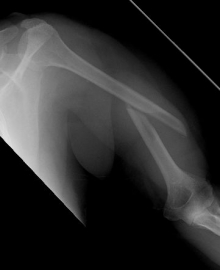

Picture: Here you can see a completely shifted upper arm fracture with a strong bend of the axis. First the operative treatment was performed by repositioning the bone and internal splinting of the fracture with a medullary nail.